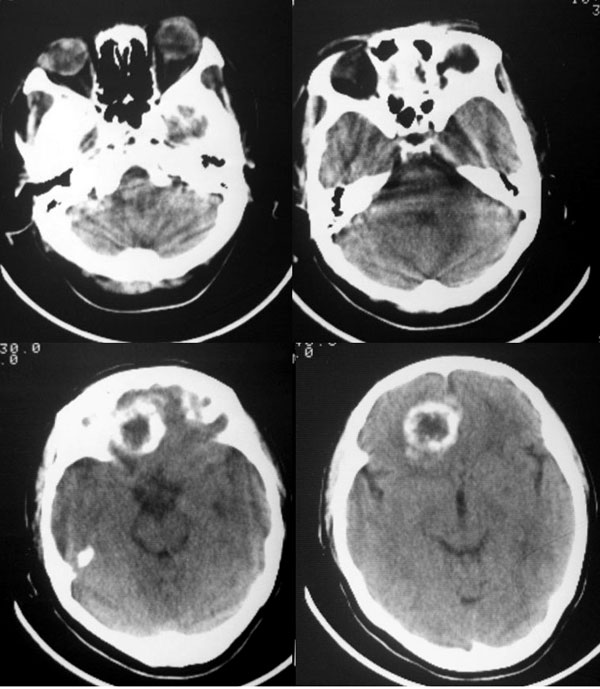

平扫前颅底区类圆形骨样高密度影,中心可见低密度影,病变向上生长突入额叶,向下生长突入筛窦,说明病灶来源于额骨水平部,脑膜瘤只能引起颅底骨质的增厚,突入筛窦的几率不大.所以我认为应该首先考虑前颅底骨软骨瘤可能大.如果病变不是来源于颅底骨质,首先应该考虑颅咽管瘤或脑膜瘤.

前颅窝底肿块,以钙化为主,周围无明显水肿,占位效应轻。考虑:骨软骨瘤或脑膜瘤。

大家看四张骨窗片:病灶最大截面在筛窦,并以此为中心向上侵入额叶,向两侧侵入双眼眶,双眼眶内侧壁亦见骨质吸收破坏,依此可确立病变位于脑外。在此部位符合上述特点的肿瘤,能想到的有骨软骨瘤或脑膜瘤,从常见病考虑,以脑膜瘤可能性大。

前颅窝底钙化性脑外肿块,右侧前床突轻度硬化,按发病部位来讲,最支持脑膜瘤。

颅咽管瘤位置太靠前且本例中央区更象软组织密度;骨软骨瘤多发生于鞍区且密度多不会如此混杂;海绵状血管瘤钙化形态多呈散发少呈如此规则环状强化,且多发于鞍区硬膜外;筛窦源性肿瘤主体应位于窦腔,窦腔骨质多有改变如嗅母;明显脑外特征则不支持脑内肿瘤如胶质瘤了。